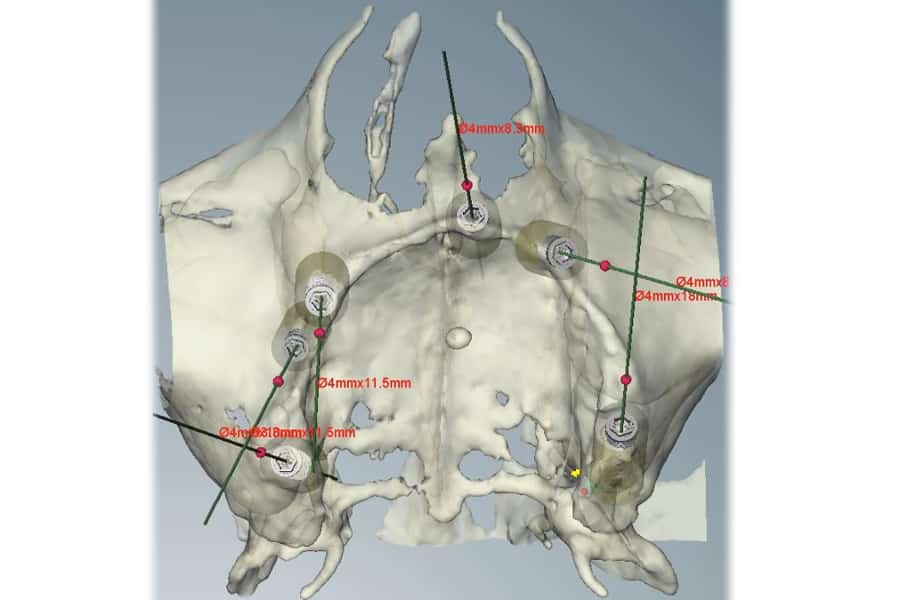

Avvalendoci di un software dedicato abbiamo creato una visualizzazione tridimensionale della TAC che ci ha permesso di pianificare chirurgicamente l’intervento di implantologia in base alle zone più favorevoli di osso residuo.

In casi simili, dove vi è una evidente e diffusa atrofia ossea, si manifesta per il chirurgo l’impossibilità ad individuare in maniera precisa le aree di osso residuo dove potere inserire gli impianti.

Al paziente, in sedazione cosciente, sono stati posizionati 5 impianti di cui uno nella zona pterigoidea, uno nella zona retro molare e gli altri 3 nella parte ossea anteriore.